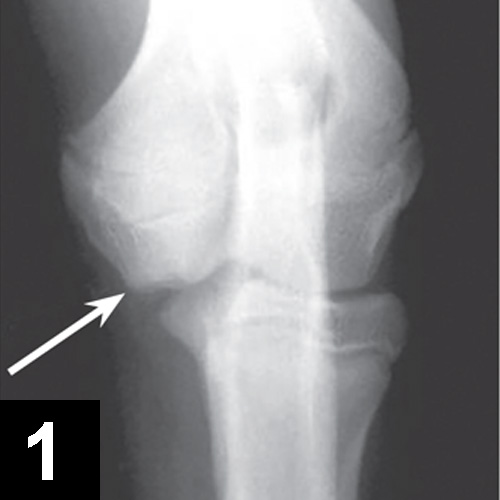

From www.cliniciansbrief.com

Medial Compartment Disease of the Elbow Clinician's Brief What Is Compartment Syndrome In Dogs What is medial compartment disease? This condition describes the loss of cartilage on both sides or throughout the medial (inside) part of the elbow joint. Medial compartment disease of the elbow (ie, the developmental abnormalities affecting the medial aspect of the canine cubital joint leading to osteoarthrosis) encompasses. Clinical relevance—compartment syndrome is a serious but rarely reported condition in dogs. What Is Compartment Syndrome In Dogs.